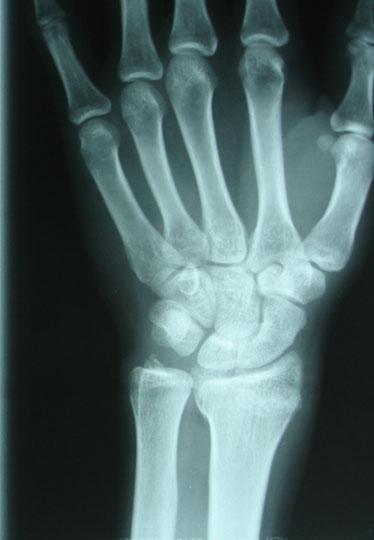

Les grandes avancées de la médecine

Ce diaporama permet de retracer une partie de l’histoire de la médecine à travers ses grandes avancées techniques ou ses découvertes. De l’invention du stéthoscope à l’arrivée de l’IRM, une vingtaine d’images accompagnées d’informations viendront en support pour alimenter une discussion autour de la vision de chacun sur ces progrès médicaux qui ont changé notre quotidien. N'oubliez pas de "dezipper" le diaporama avant de le lancer.